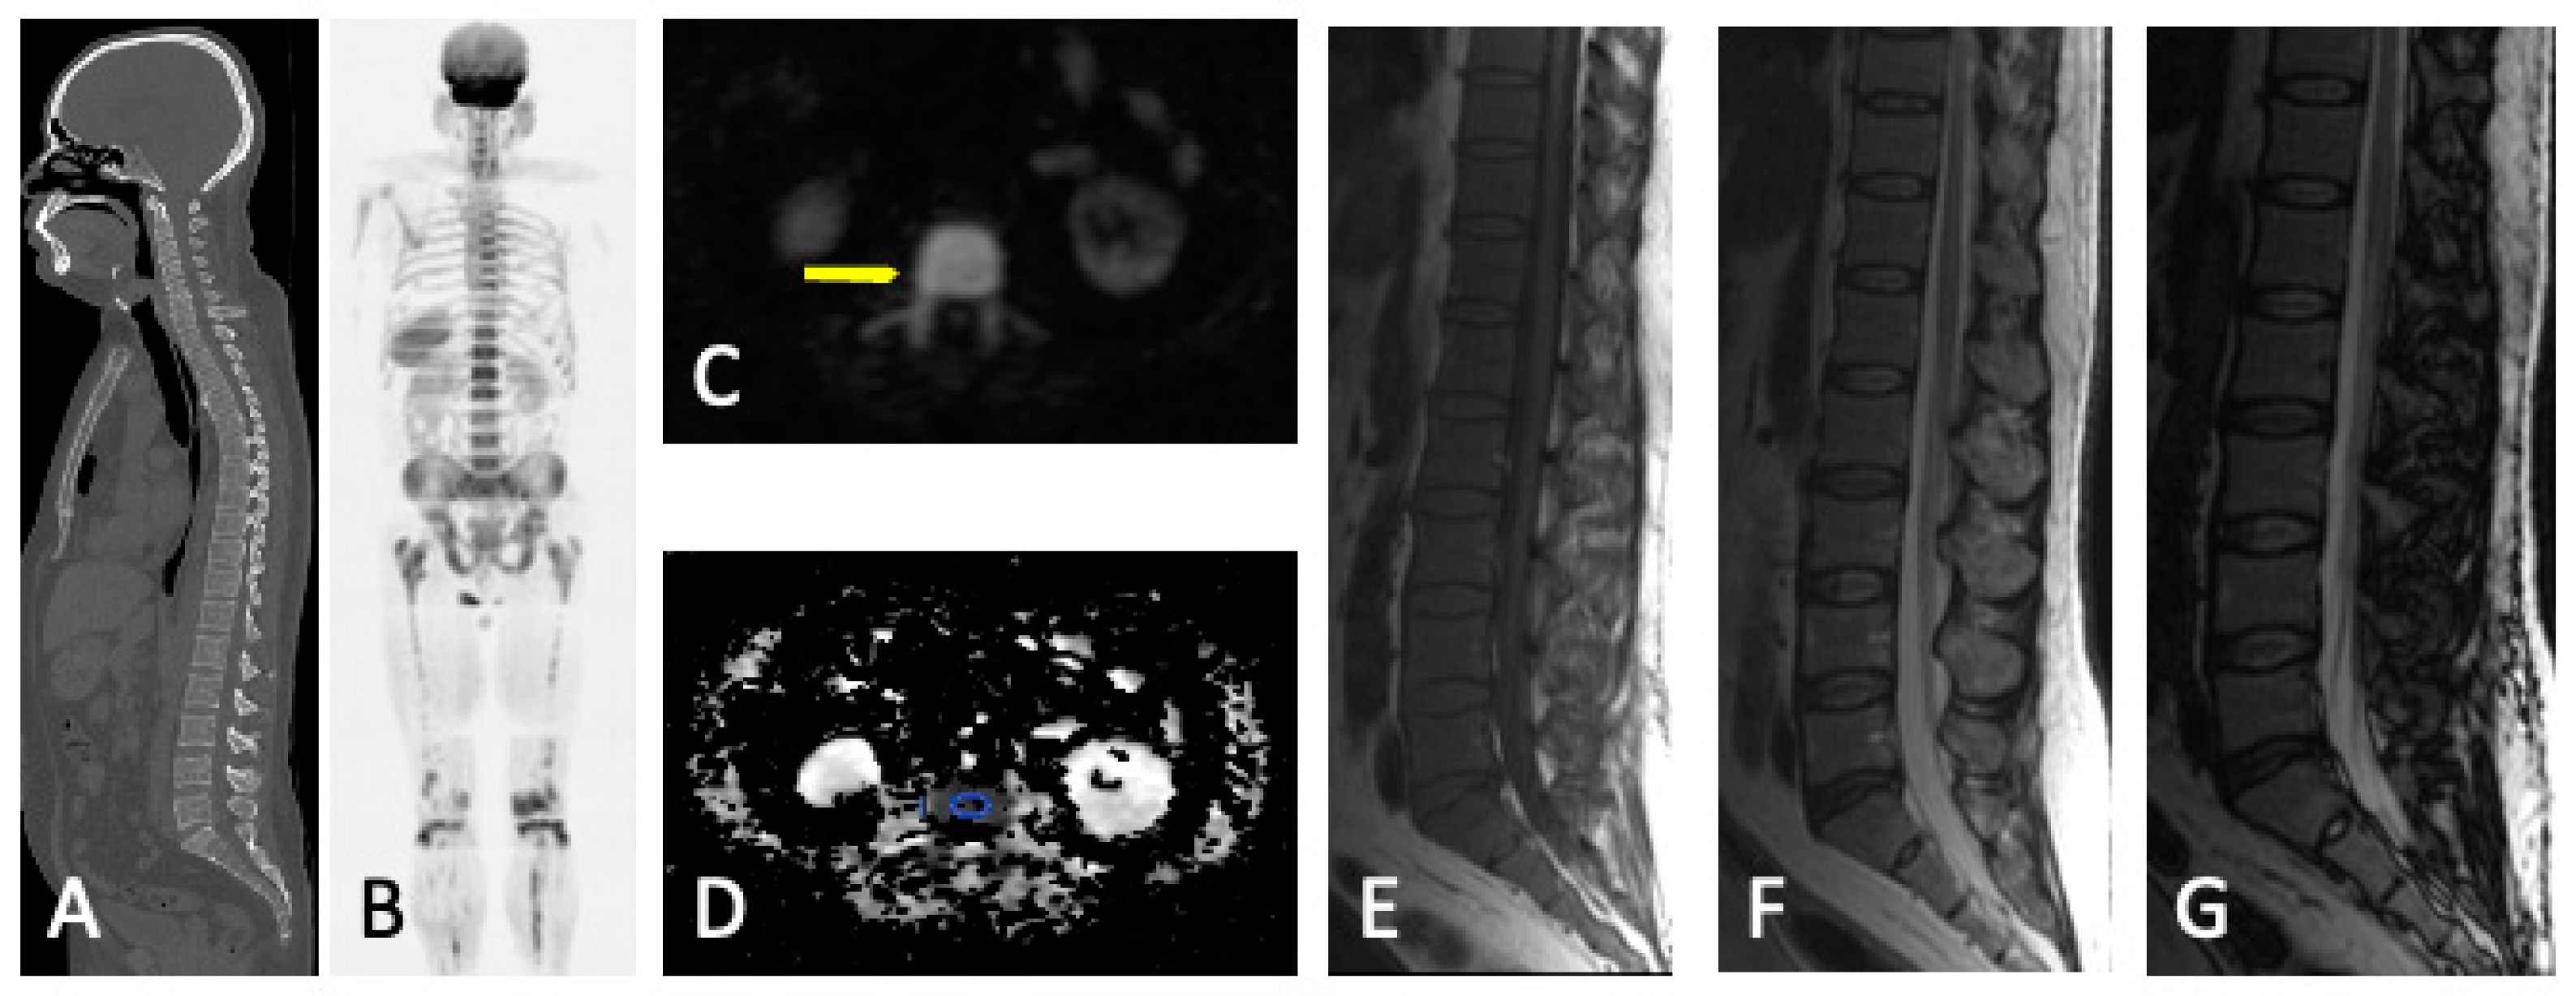

- Diffuse pattern: Diffuse disease can be suspected from a diffuse decreased signal on T1WI (either iso- or hypointense to intervertebral discs and muscle) and a diffuse increased signal throughout the marrow on T2FSWI, STIR, or high b-value DWI. Marrow ADC values above 600–700 μm2/s in a nontreated and newly diagnosed patient with MM could be used to increase confidence for the diagnosis of diffuse marrow involvement [33] (Figure 7). Due to potential false-positive findings, diffuse disease in imaging must be supported by bone marrow trephine biopsy [26].